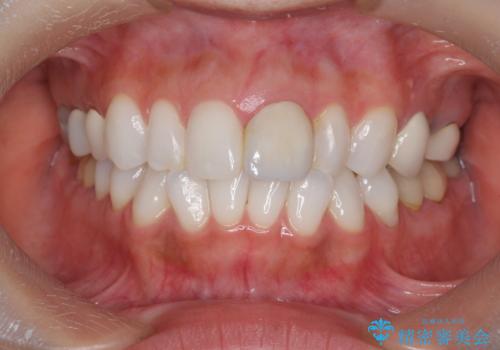

- 欠けてしまった前歯のラミネートベニヤと見た目の改善を求めて来院されました。

歯の大きさの不揃いと、虫歯の再発を認めたためラミネートのやりかえではなく一挙に問題の解決のできるジルコニアクラウンでの治療を計画します。

歯の大きさの不揃いが改善されただけでなく、色調もよくなり審美性をしっかりと改善することができました。